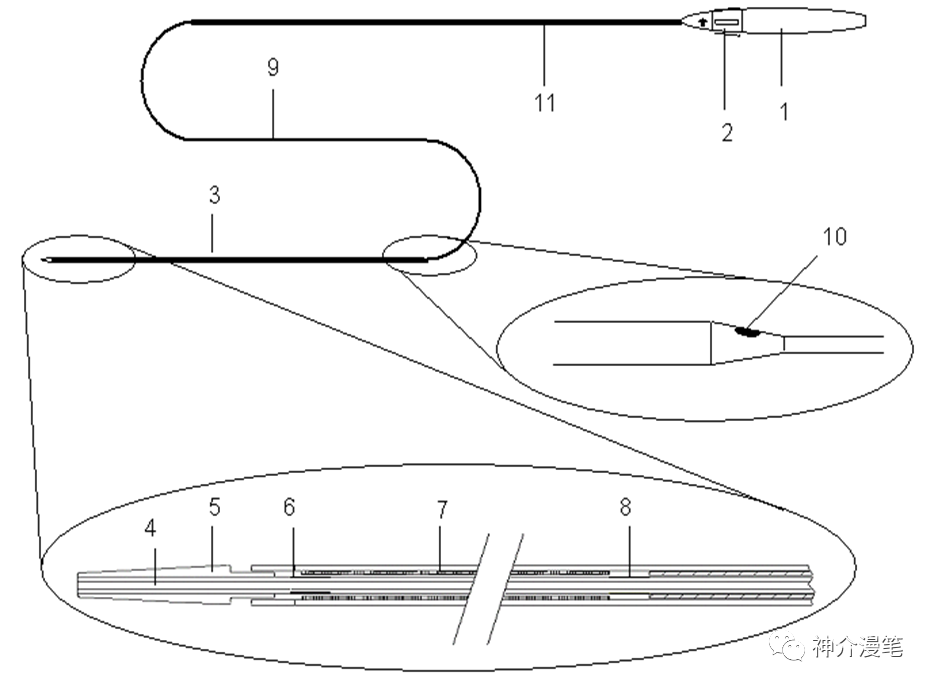

关键词:开环,镍钛,快交,无锥形支架。另外PRICISE支架8以下可以使用6F导引导管进行释放,这在部分通路迂曲的血管条件下尤为重要。支架释放过程不需要推挤支架,只需要把住推送杆后等张力扒开支架即可。

说一下雅培的Xpert支架吧,整体来说是个挺有想法的支架。号称复合设计,其实归根还是个开环支架,最大的特点是壁薄,外径小,可以经过更小的导管和鞘输送,对于迂曲通路这是一个好的设计。

3-6的支架可以使用4F鞘或6Fguiding进行释放,下图为其常见支架型号。